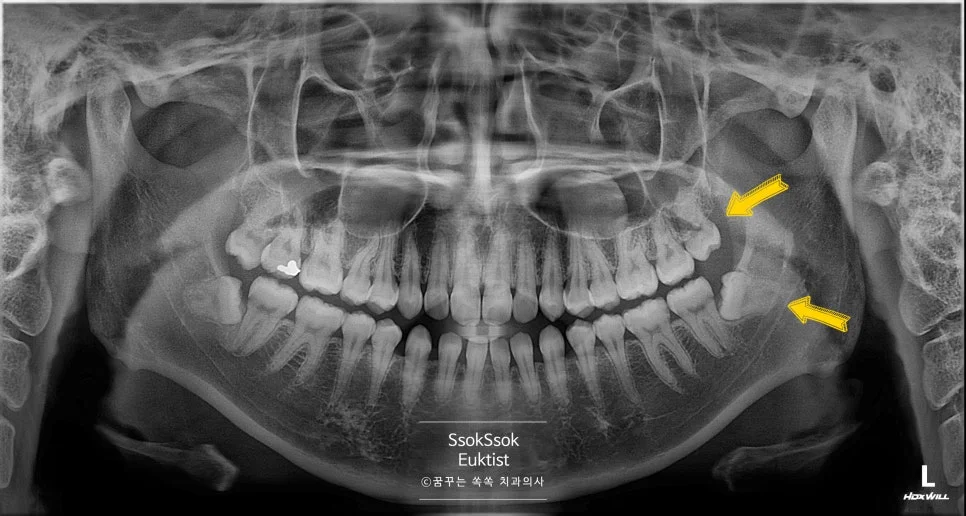

환자분께선 왼쪽 위, 아래 사랑니(좌측 상악 제3대구치와 좌측 하악 제3대구치)가 통증이 심하여 발치를 원하셨습니다.

상악 왼쪽 사랑니 구강 내 사진

파노라마와 CBCT(Cone Beam CT) 촬영 결과, 왼쪽 위 사랑니는 쉽게 발치할 수 있는 사랑니였고, 왼쪽 아래 사랑니의 경우 신경관과 1mm 이내로 붙어 있는 신경 손상의 위험이 있는 매복 사랑니입니다.